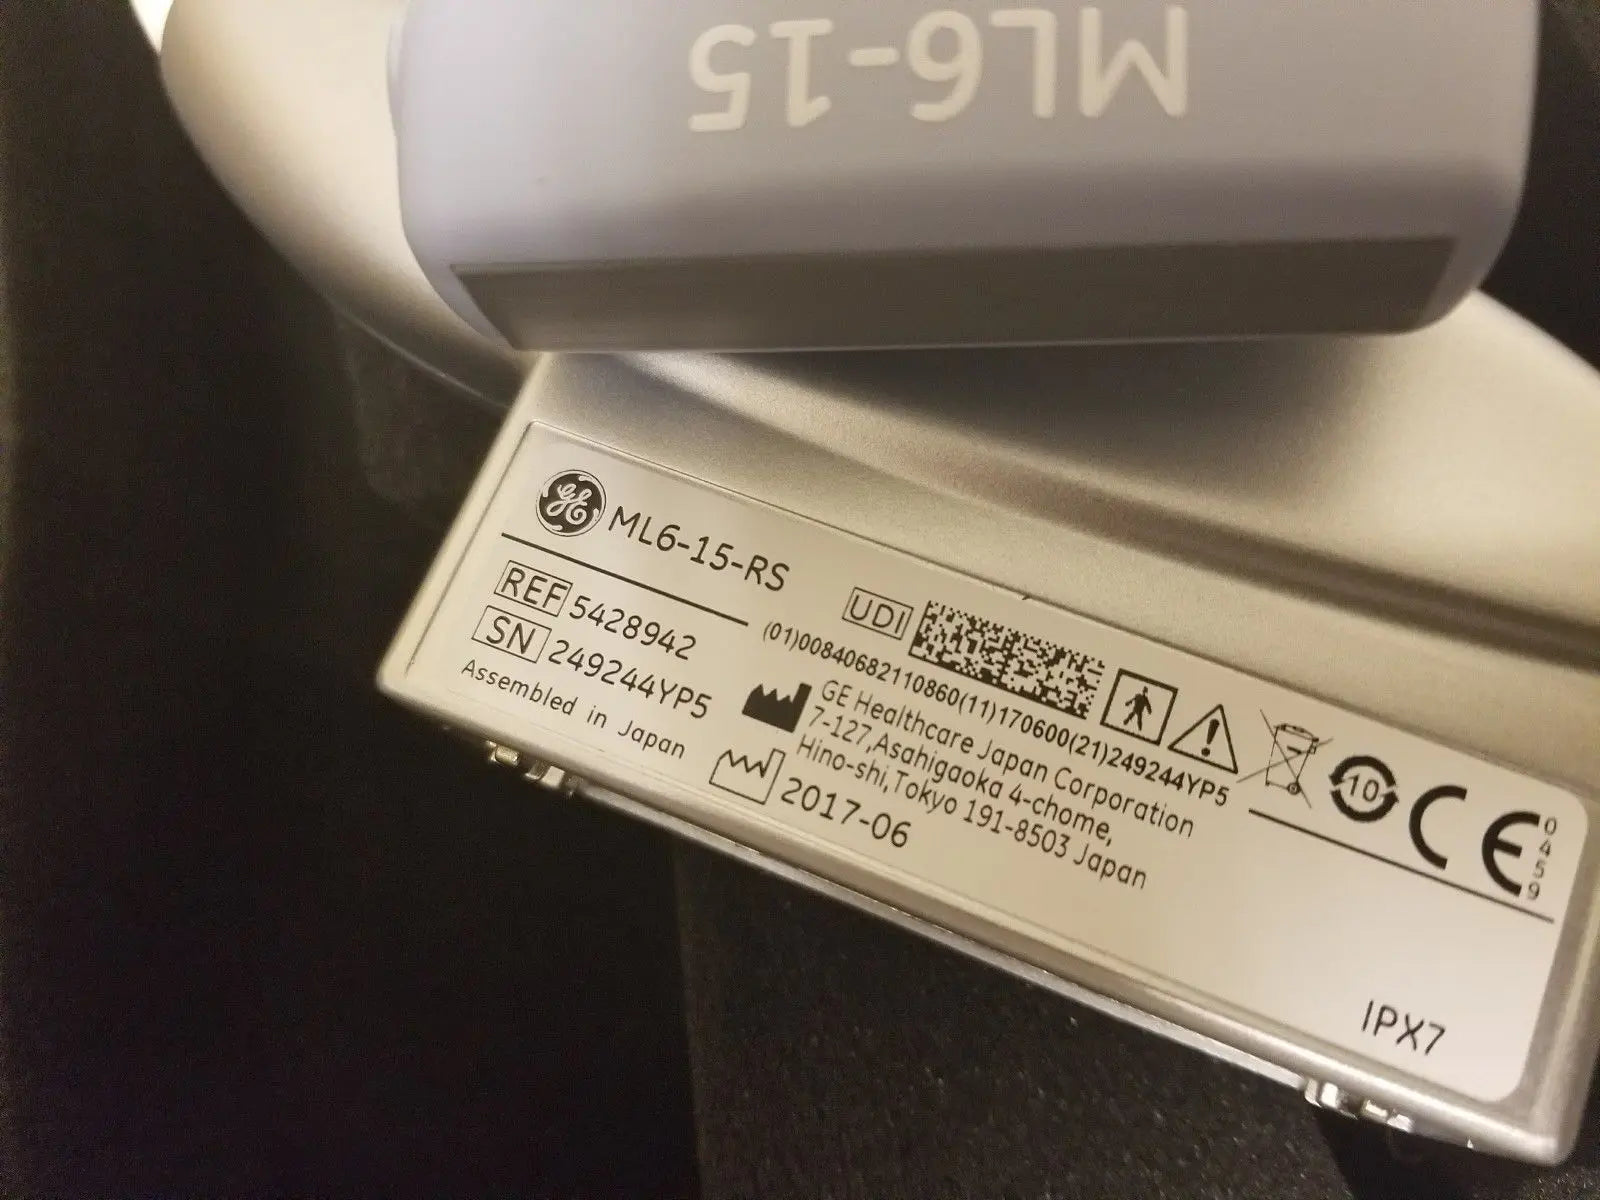

DIAGNOSTIC ULTRASOUND MACHINES FOR SALE

2017 GE ML6-15 -RS for GE S8 ,S6 Ultrasound

Sale price$ 7,675.18